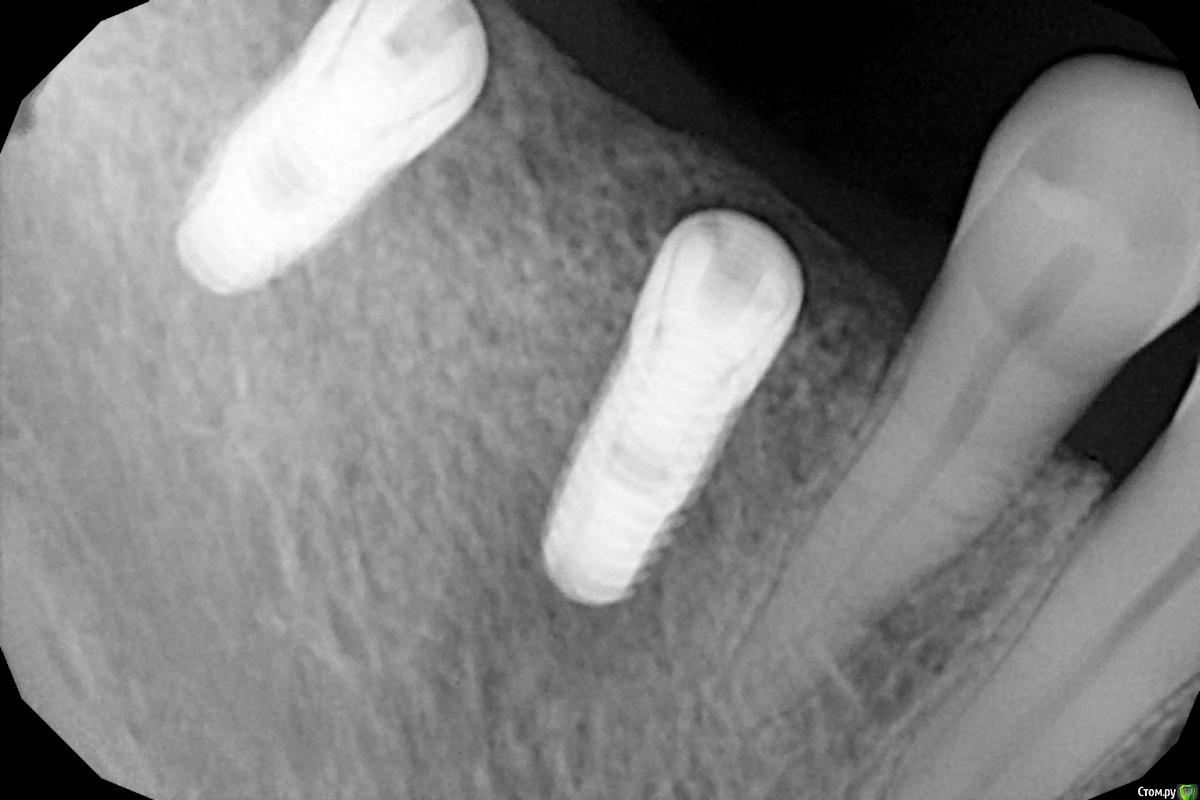

Женька Опубликовано 21 января, 2021 Автор Поделиться Опубликовано 21 января, 2021 Все должно хорошо закончится, вы переживаете, не безразлично, это хорошо. Я против слишком больших торков, особенно в плотной кости и узком гребне. Ха! Самую страшную КТ показал Колесников, типа " дед" кошмарит новичка))))Снимки подписаны датами. Есть же какая то динамика, что думаете? И всё-же, какое усилие на выкручивание считать приемлемым? Я же правильно понимаю, что 45 это про первичную стабильность. А для вторичной это пшик? Ссылка на комментарий

red_butler Опубликовано 21 января, 2021 Поделиться Опубликовано 21 января, 2021 на снимках все нормально, торк для проверки должен быть как минимум равен торку при фиксации винта абатмента, у дентиума это 30 или 35Н/см 2 Ссылка на комментарий

Irouil Опубликовано 21 января, 2021 Поделиться Опубликовано 21 января, 2021 (изменено) 35 давайте, если винт не интегрирован - никакой "вторичной" нет, так что там до 35 не дойдёт, если интегрирован - ему действительно пшик Снимки огонь, но я ставлю на то, что медиальный выкрутите( Изменено 21 января, 2021 пользователем Irouil Ссылка на комментарий

Женька Опубликовано 21 января, 2021 Автор Поделиться Опубликовано 21 января, 2021 35 давайте, если винт не интегрирован - никакой "вторичной" нет, так что там до 35 не дойдёт, если интегрирован - ему действительно пшик Снимки огонь, но я ставлю на то, что медиальный выкрутите(Тоже думаю, что выкручу) Ссылка на комментарий